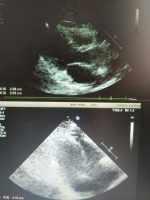

腹瀉--腹部B超:膽囊內(nèi)膜不光滑 關(guān)鍵疾?。?a href="http://m.akellydesign.com/tags/so/腹瀉-4-1.html" target="_blank">腹瀉 現(xiàn)病史【一般資料】女性,53歲,職工【主訴】腹瀉1天入院?!粳F(xiàn)病史】入院前1天,進食不潔食物后出現(xiàn)腹瀉,為3次,為稀水樣便,量多,無明顯腹痛,無發(fā)熱,有納差,伴惡心,無嘔吐;無頭暈、頭痛,無意識障礙,無二便失禁,無流涎,飲食無嗆咳;無咳嗽、咳痰,無胸痛、胸悶。為求診治,來我院就診,以“急性腸炎”收入院。自本次發(fā)病來,精神如常,食欲尚可,睡眠及二便如?!炯韧贰考韧跔顒用}粥樣硬化性心臟病心絞痛病史2年;否認肝炎、結(jié)核及其他傳染病病史;無外傷、手術(shù)及輸血史;無食物及藥物過敏史;預(yù)防接種史不詳?!静轶w...